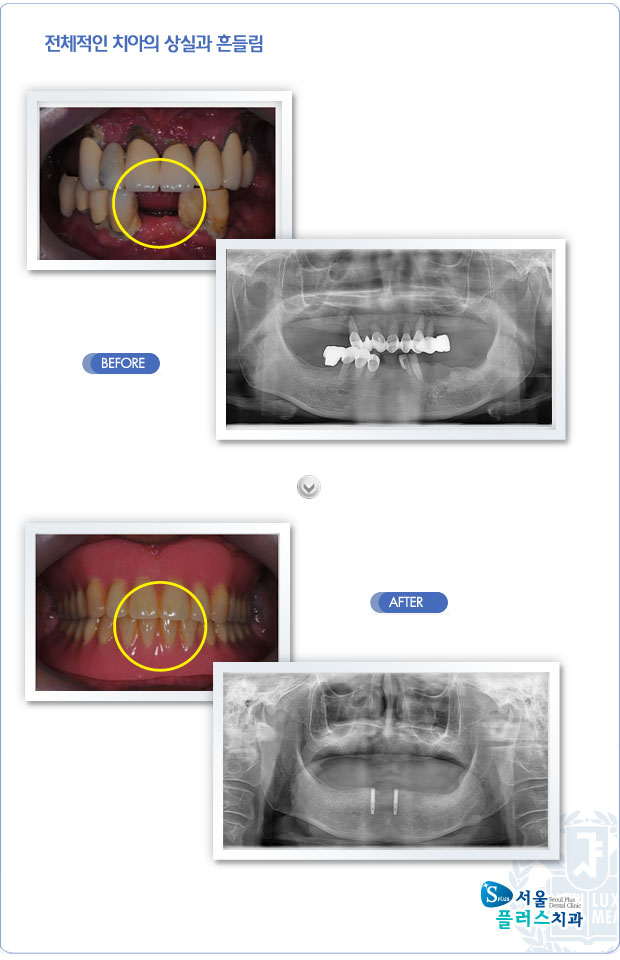

[임플란트] 전체적인 치아의 상실과 흔들림